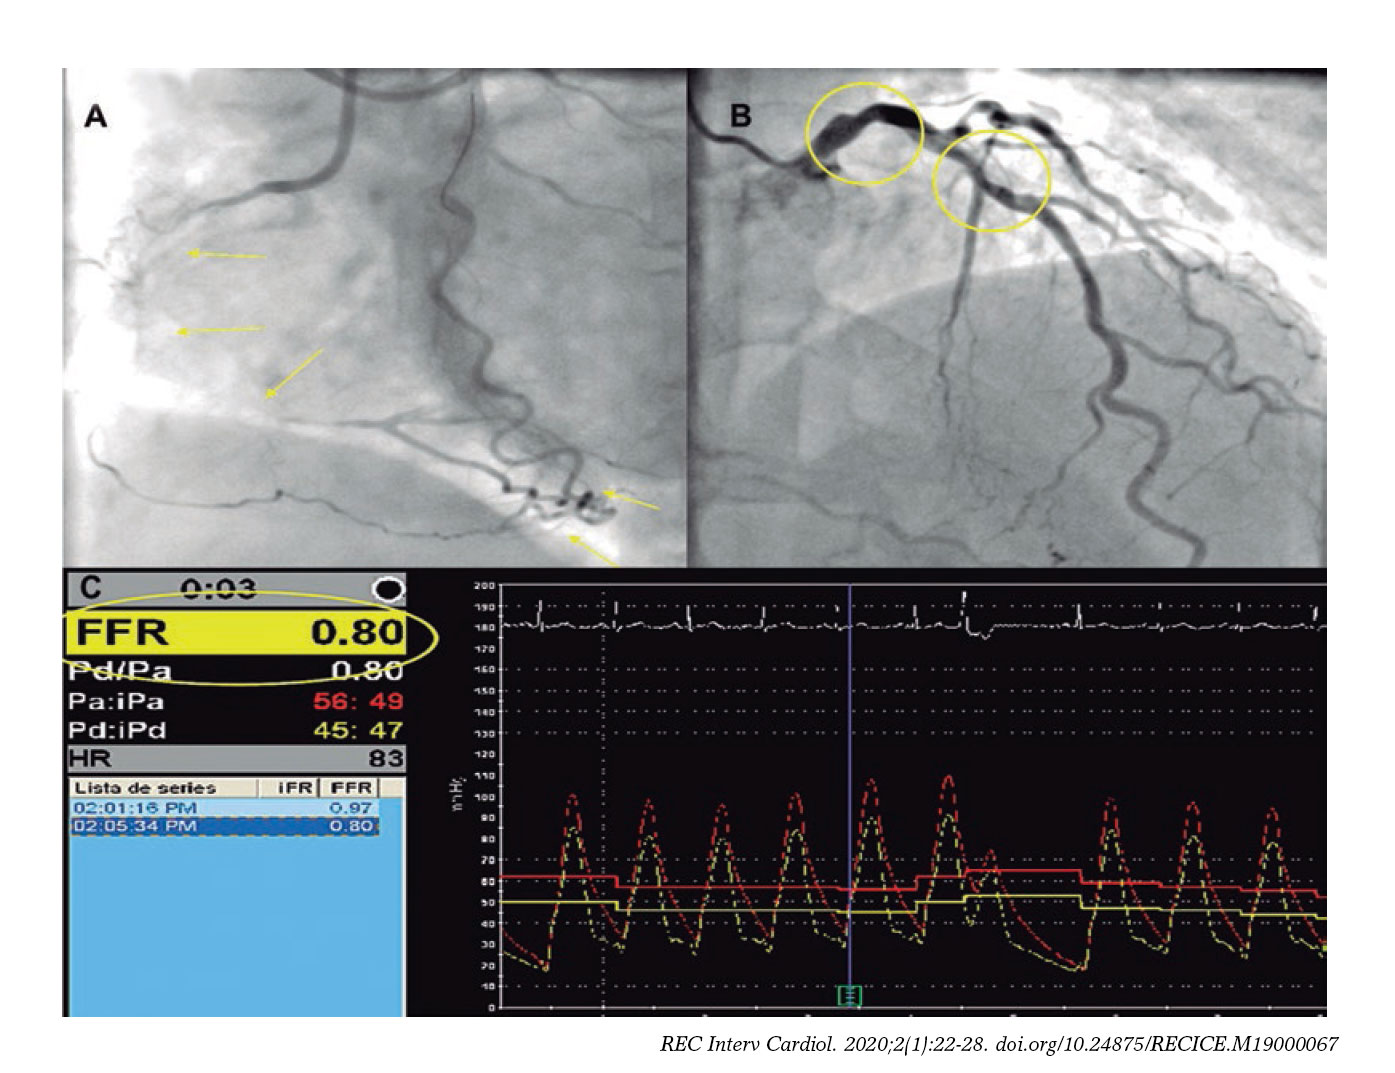

Functional Assessment Of Intermediate Lesions Of Collateral Donor Artery In Chronic Total Coronary Occlusions Ischemic Heart Disease Original Article

www.recintervcardiol.org

Limitation Of Fractional Flow Reserve In Evaluating Coronary Artery Myocardial Bridge Journal Of Invasive Cardiology

www.invasivecardiology.com